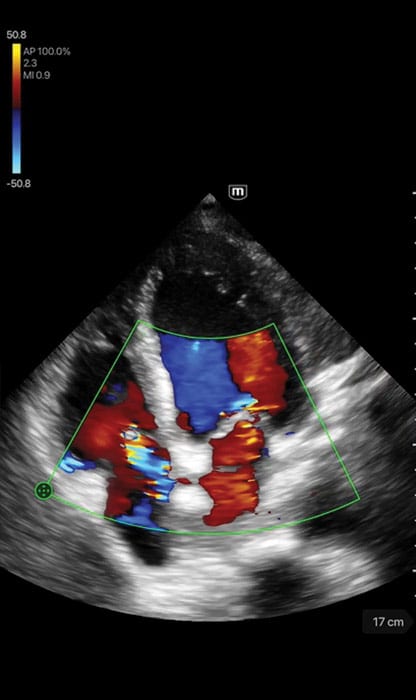

- Scanning modes: B-mode, M-mode, Color Doppler, Power Doppler, PW, and Tissue Doppler Imaging

- Dedicated presets for Cardiac, Abdomen, Lung, Transcranial Imaging (TCI), Emergency Medicine (EM), Trauma (FAST), EM Abdominal

- Aortic Aneurysm (AAA), Bladder, OB/GYN, and Vascular

Clinical Images